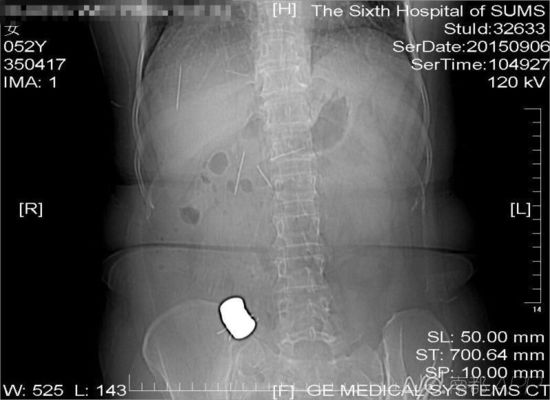

CT檢查結(jié)果中顯示,老人腹中有多個(gè)金屬異物和散落的繡花針

進(jìn)行的CT檢查結(jié)果顯示,黃姨腹中有多個(gè)金屬異物和散落的繡花針。主管醫(yī)生黃俊博士介紹,這些針分別位于黃姨小腸內(nèi),部分已經(jīng)穿出小腸散播于腹腔內(nèi),還有部分金屬異物,最大的一塊上附著了數(shù)根斷針,有一根插進(jìn)了胰腺,剩下的一根在脊柱附近,每枚約長4厘米。